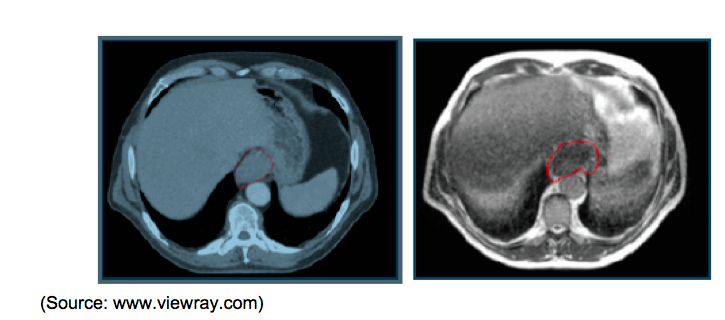

Adenocarcinoma of Distal Esophagus: The image above left shows the GTV delineated by the physician from the CT simulation. The image above right from the MRIdian® simulation shows the updated GTV. A large area of this target was not visible on the CT and therefore could have been missed without the MRI.

Sigmoid Colon Cancer with Bladder Invasion; A large sigmoid tumor that was invading the bladder could be located and accurately tracked despite its motion using the MRIdian system.